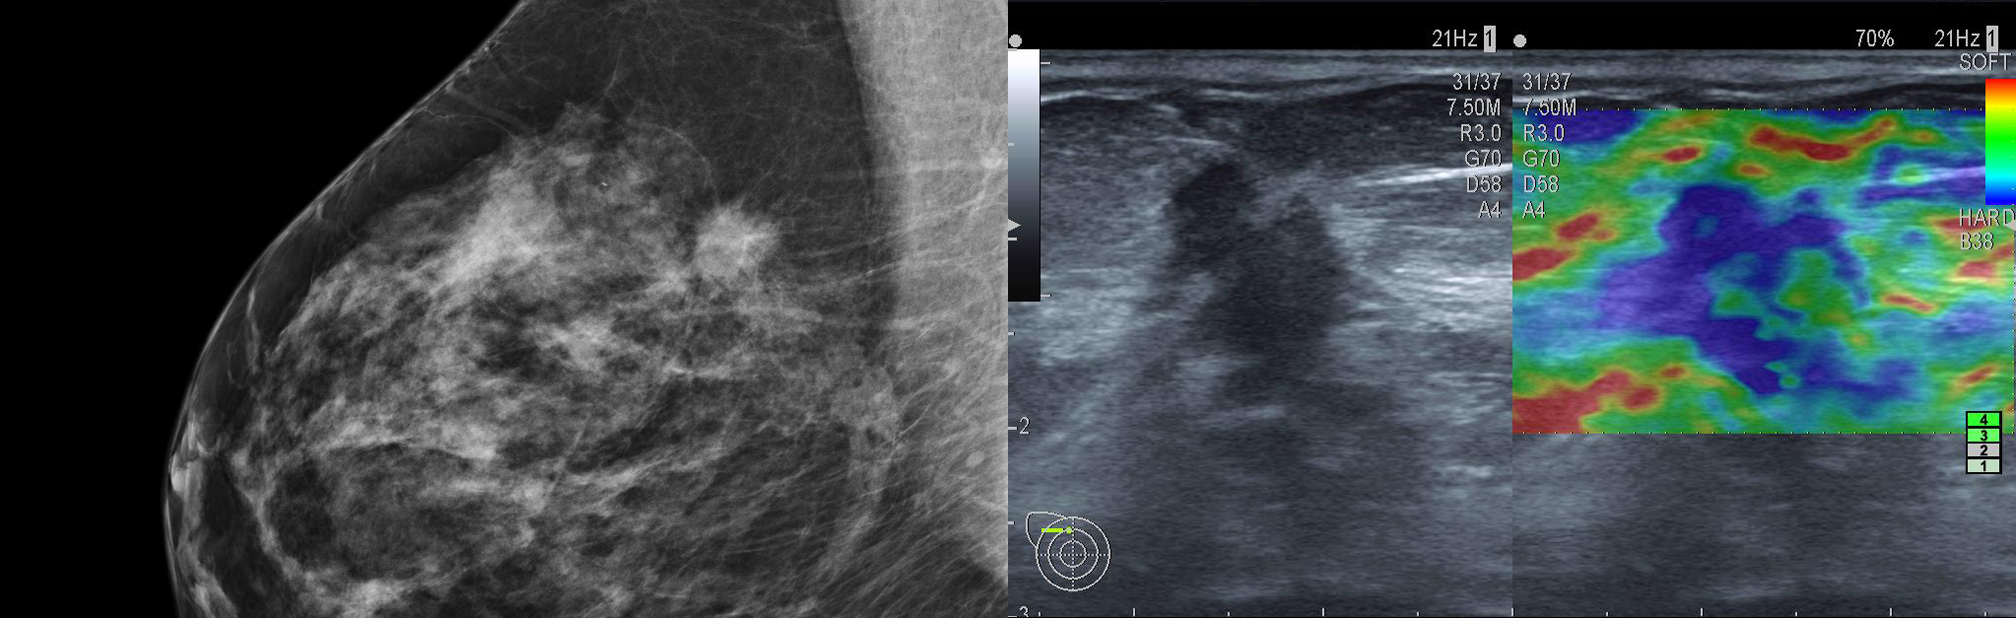

auffälliger Herd in der Mammographie und Elastographie